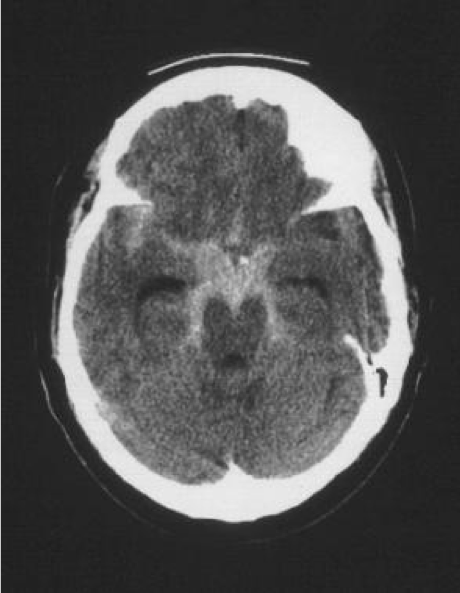

With Jennifer having such clear-cut symptoms of SAH, the team will do some bloodwork and order a CT head to check for obvious bleeding. The resident is confident that the CT will find a bleed, as CT will find a subarachnoid hemorrhage nearly 100% of the time within 6h of the onset of symptoms. However, when suspicion is high for SAH and the CT is normal, when symptoms developed >6h prior to presentation, or in other specific circumstances, a lumbar puncture (“spinal tap”) is performed to look for blood, or the products of hemoglobin breakdown (“xanthochromia”) in the cerebral spinal fluid.

As the resident finishes her explanation. The Jennifer returns from CT and the following image is obtained, showing obvious bleeding into the subarachnoid space around the base of the brain. The EM resident calls Neurosurgery to arrange cerebral angiography and admission.

Medscape – SAH in the basal cisterns.

The physician tells you that most often the aneurysm is in the anterior circulation of the Circle of Willis, near a bifurcation point. In Jennifer’s case, it will turn out that the aneurysm is at the junction of the right internal carotid and the anterior communicating artery. They also tell you that the most common complications from an SAH is rebleeding and vasospasm, and she will spend many days in the ICU as they struggle to control blood pressure and blood chemistry and try to maintain cerebral perfusion pressure.